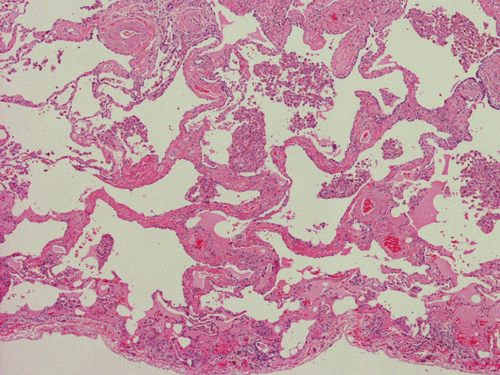

At scanning magnification (Panel A), the lung parenchyma is replaced by some coalescing fibrous nodules. The degree of involvement is variable at different fragments (Panel B and C). In the less affected areas, there are some fibrotic thickening of the septa (Panel C). In some areas, the changes are minimal and the pleural appear to be uninvolved (Panel D and E). In low to medium magnifications, these nodules of fibrosis contains a large number of hemosiderin laden macrophages (Panel F and G) admixed with fibrous tissue. The diagnostic tissue, however, is present in areas with increased cellularity. In these areas, there is a background of cells with a moderate amount of cytoplasm and bland nuclei. Some of these nuclei have kidney shape (arrow in Panel H). In some areas, many of the nuclei have a deep nuclear groove that resemble a coffee bean (arrow in Panel I). In the third type of areas, the nuclear grooving is not distinct (Panel J). Prominent eosinophilic infiltrations are almost always present. Immunohistochemistry on CD1a revealed many positive cells (Panel L). Also present in the specimen are multiple small blood vessels with thickened intima (Panel K). A Movat pentachrome stain demonstrates an internal elastic layer in these vessels and confirms that these are arteries (Panel M and N).

In the early stage of PLCH, there are interstitial infiltrates composed of LCs, lymphocytes, macrophages, eosinophils, plasma cells and fibroblasts 4. The infiltrates enlarge to form nodules centered on the small airways. Brown pigmented macrophages (smokers macrophages) are present in and around the nodules. Eosinophils tend to localize at the innermost layer of the nodules, where LCs can be most easily found in the thickened interstitium. Associated patchy interstitial and airspace organization or respiratory bronchiolitis may be present. Other smoking related changes are also common. Cavitation often occurs within the nodules which represents either an airway remenant or de novo cavitation as the inflammatory infiltrate enlarges. There is centripetal replacement of the nodules by fibroblasts which produce the classic stellate lesions of PLCH. As the disease progresses, the number of nodules, cavitary granulomas and fibrotic scars increase in number.

In the end stage, the exhausted lesions are predominantly fibrotic and largely depleted of LCs. In some regions, the fibrosis may surround cystic spaces of variable diameter to form large areas of honeycombing. This is especially predominant in the upper lobes. In cases where parenchymal scaring is present, the pulmonary function will be largely compromised. At this stage, both pulmonary function tests and radiologic findings may suggest diffuse lung disease, but biopsy will show stellate fibrotic lesions centered on the terminal airways with no identifiable interstitial inflammation. Pulmonary vasculopathy (in areas of lung remote from parenchymal nodules) is also seen in late stage PLCH. Vasculopathy manifests as intimal fibrosis, medial hypertrophy or luminal obliteration involving both venules and arteries. This may account for pulmonary hypertension seen late in PLCH.